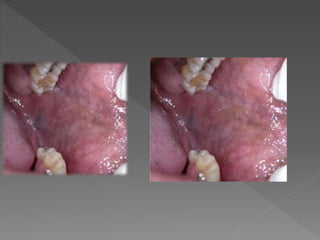

Gingivivoestomatitis

VHS

 Homigueo

 Ardor o dolor

 Labio superior +

 Paladar

 Gingiva

 Se reactiva virus y no

infección

 Estrés, luz solar, frio, baja

defensas

 Tx Aciclovir

 Sana en 2 semanas

 No deja cicatriz

 Autoinoculacion

 Dx diferencial: MPB, Varicela,

Herpangina .